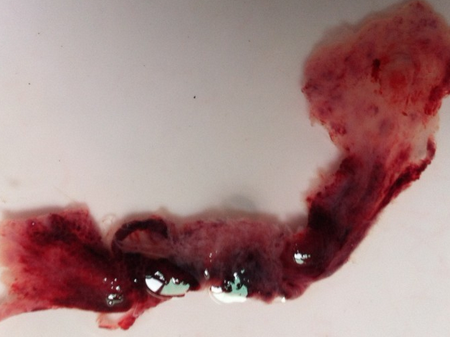

孕囊掉落是指懷孕初期,由于某些原因,孕囊與子宮壁分離并排出體外的過程,這種情況通常伴隨著出血和腹痛等癥狀。

為了更好地理解孕囊掉落的過程,我們分享一些相關的圖片(此處可插入孕囊掉落的圖片),這些圖片可以幫助讀者直觀地了解孕囊的外觀、大小以及排出過程。